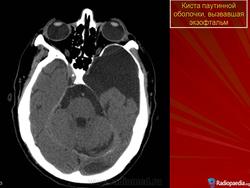

До 4 % кист локализуется глубоко в орбите. Это так называемая котомковидная дермоидная киста орбиты, описанная Kronlein в конце XIX в. Образование состоит из трех частей: головка кисты — ампулообразное расширение — находится за пределами тарзоорбитальной фасции в глубине орбиты, хвост кисты — в височной ямке, а перешеек — в области лобно-скулового шва. Для такой локализации характерно длительное (иногда в течение 20—30 лет) постепенное увеличение экзофтальма. Опухоль, смещая глаз в сторону, ограничивает функции экстраокулярных мышц, появляется диплопия. Увеличение экзофтальма до 7— 14 мм сопровождается постоянными распирающими болями в орбите. Нарушение зрения может быть обусловлено изменением рефракции вследствие как деформации глаза, так и развивающейся первичной атрофии зрительного нерва. Котомковидную кисту обычно диагностируют после 15 лет. Длительно существующая киста может распространяться в полость черепа. Диагноз подтверждают с помощью рентгенографии орбиты (выявляют истончение и углубление костного края орбиты в зоне расположения кисты). Наиболее информативна компьютерная томография, при которой хорошо визуализируются не только измененные костные стенки, но и сама киста с капсулой.